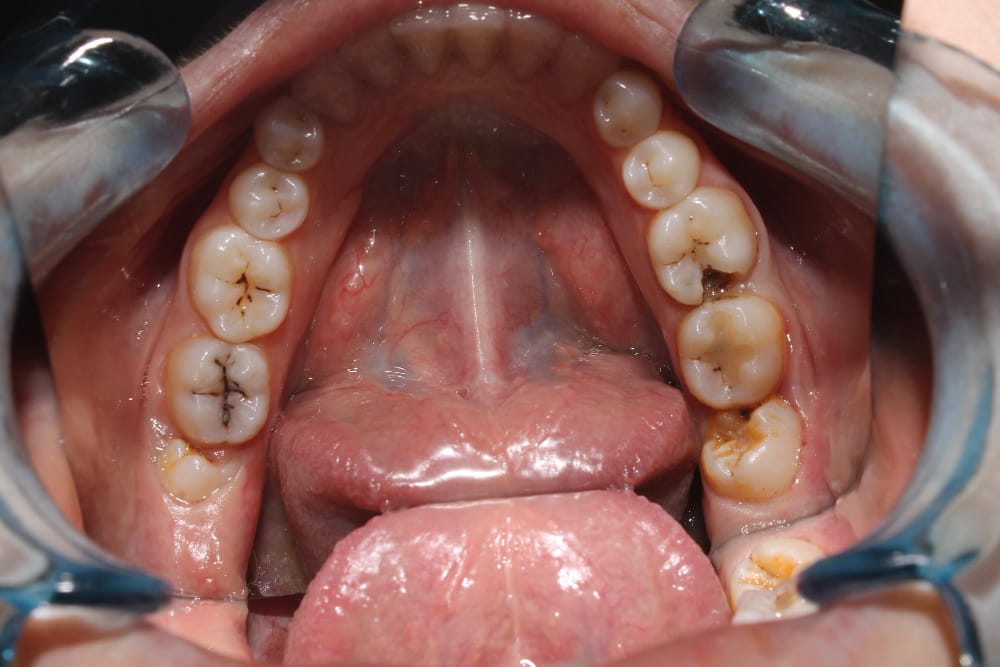

Gingivitis is the early stage of gum disease, characterized by inflammation and irritation of the gums. It occurs when plaque builds up on your teeth, leading to bacterial growth that irritates your gum tissue.

Gum disease, medically known as periodontitis, is a more advanced condition that can develop from untreated gingivitis. It’s an infection of the gums that can cause damage to your gums and bones supporting your teeth.

Symptoms of Gum Disease:

- Tooth sensitivity

- Receding gums

- Loose or mobile teeth

- Tooth loss